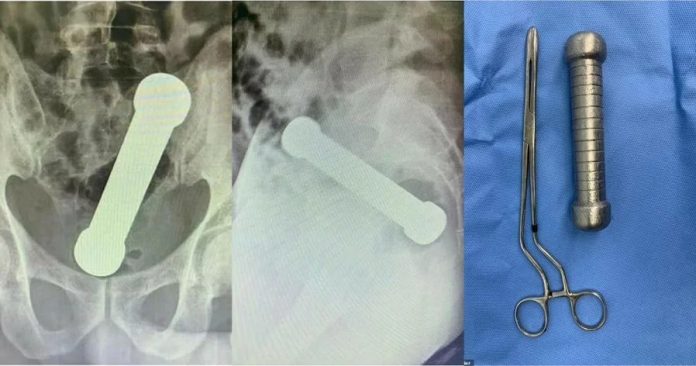

根据《每日邮报》报导,居住在亚马逊州首府玛瑙斯(Manaus)的54岁男子,日前把一个2公斤重的哑铃塞进肛门后,无法自行取出,忍耐了2天,才因为身体不适就医,他抱怨自己有腹痛、恶心想吐、无法排便等症状,不过医生内诊时看不出任何异状,于是安排男子进行腹部X光检查。

医生透露,男子在体检期间相当不配合,所以猜测他是因为“性行为”造成身体出问题。而X光片显示,有一个长约20公分的哑铃,卡在男子的直肠与结肠交接处,尽管医生想透过手术镊子夹取,但始终无法夹出哑铃,无可奈何之下,医生只好亲自“动手”,把手臂一部分伸入患者的直肠中,才终于顺利取出哑铃。